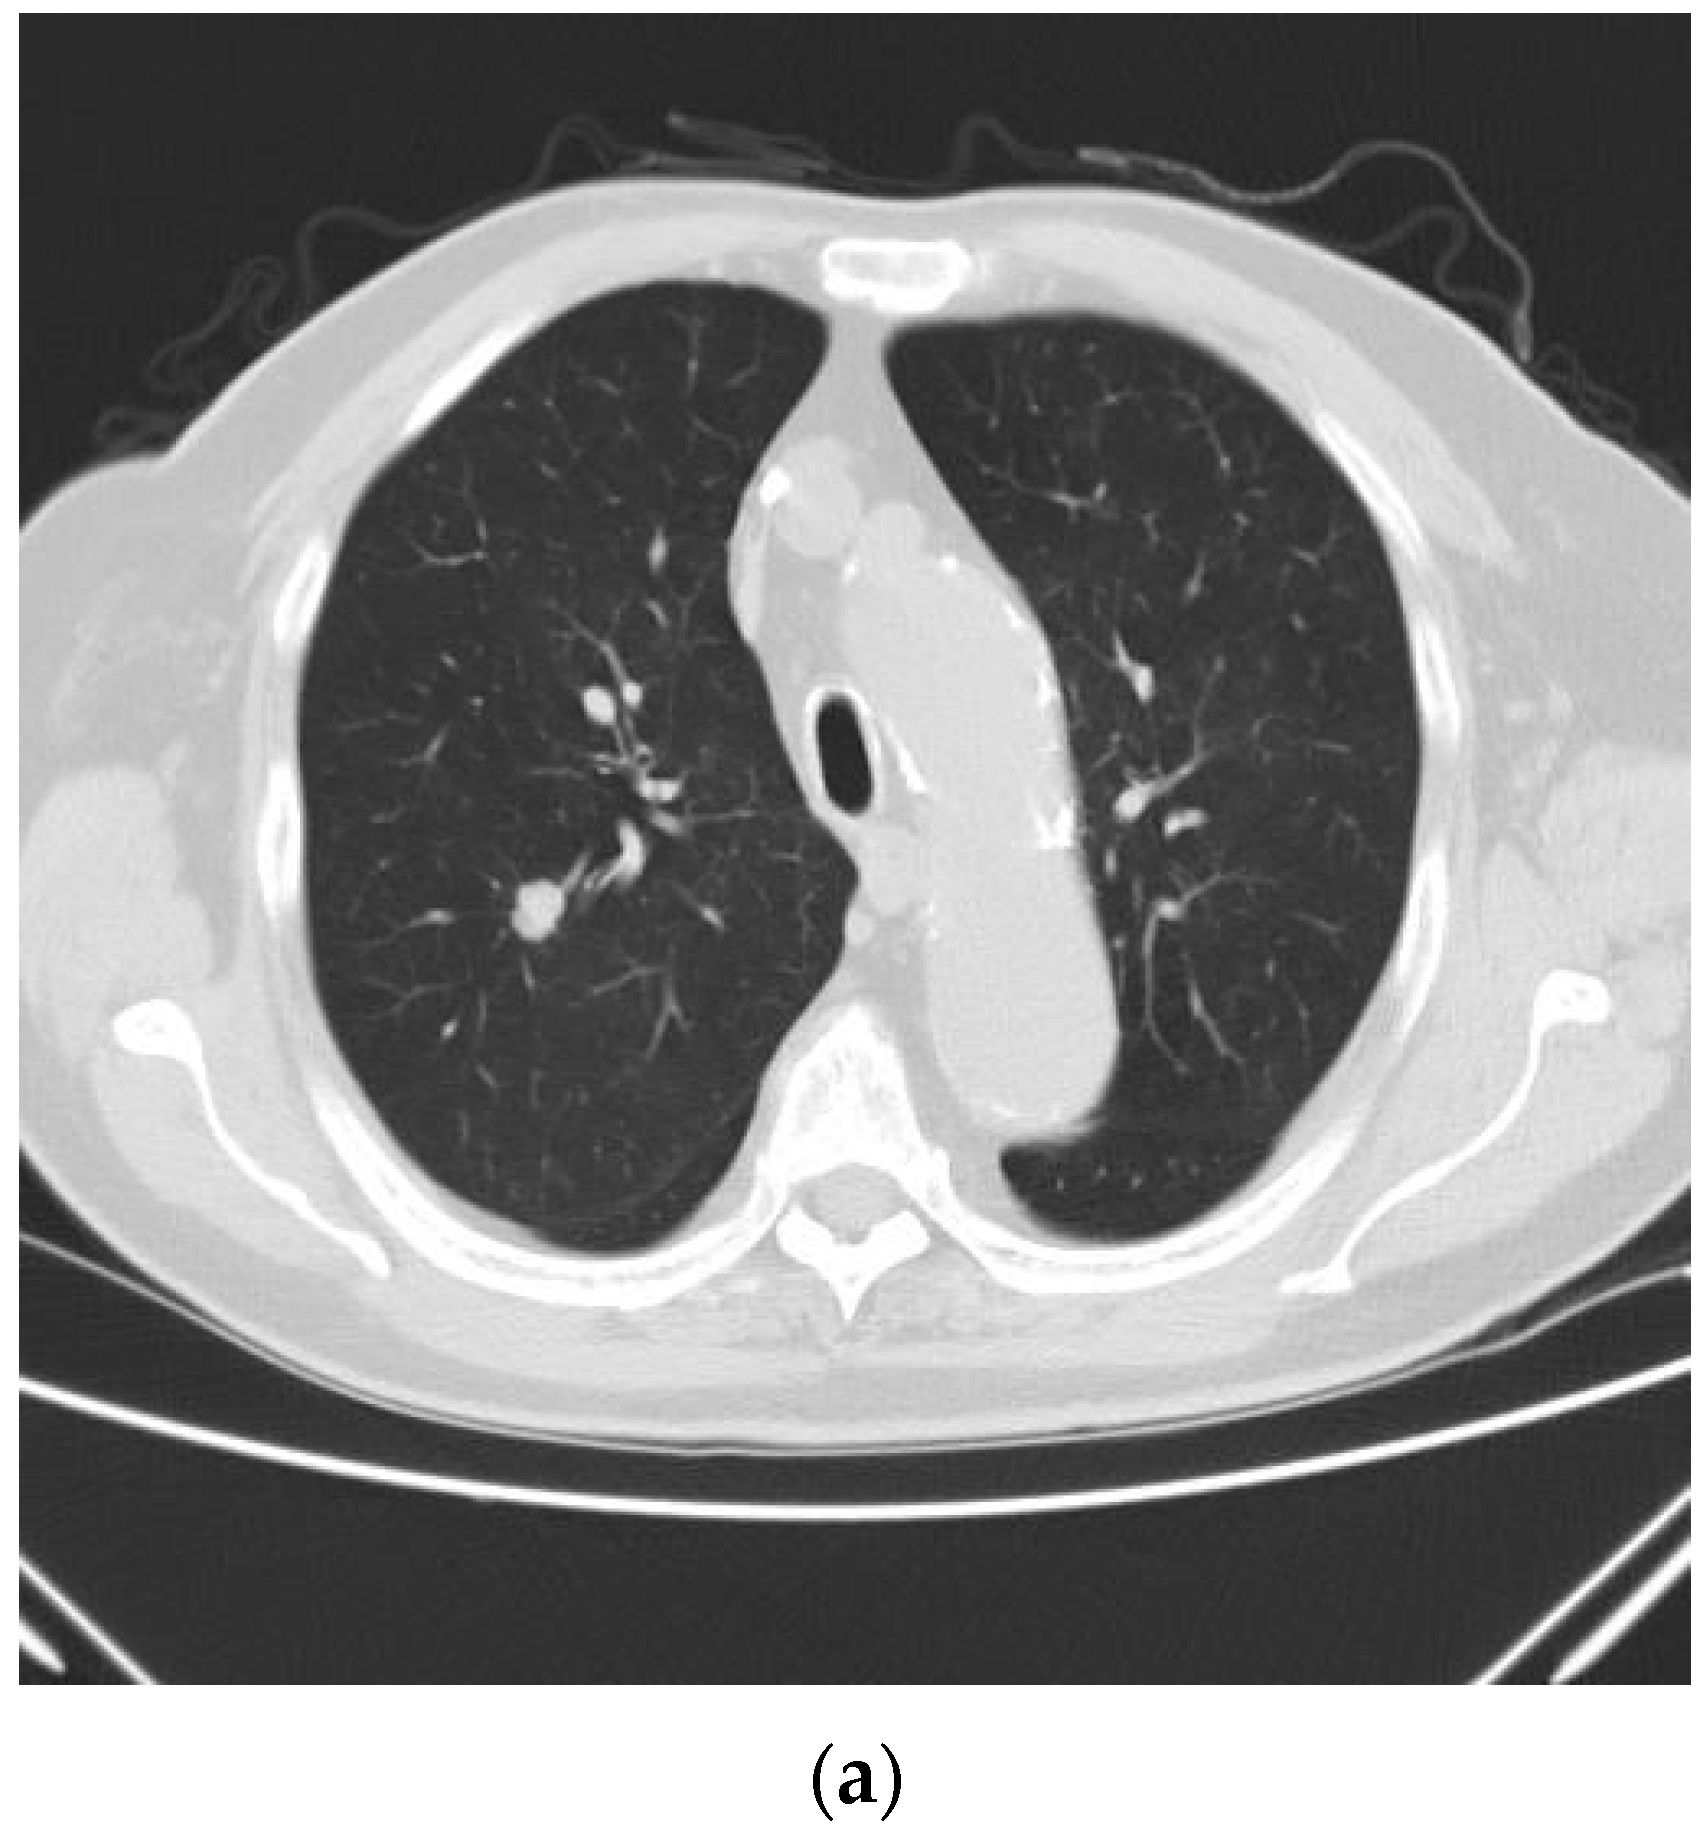

2.2. Technique for Drainless Uniportal VATS Wedge Resection